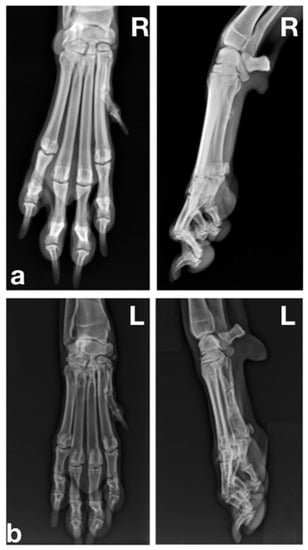

2.1.2. Radiographic Examination

2.2.2. Radiographic Examination

2.3.2. Radiographic Examination